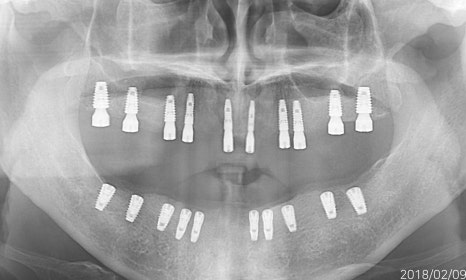

무치악환자를 위한 전악임플란트

전악임플란트 중점 치료

<참고이미지> 무치악 환자의 임플란트 치료 사례 / 환자에 따라 치료결과는 다를 수 있으며 임플란트 주위염 등이 발생할 수 있습니다.

무치악 환자에게 적용시 치아의 기능을 일정수준으로 회복할 수 있는 치료입니다.

20.09.19 경과체크 / 무치악 임플란트 치료 / 환자에 따라 치료결과는 다를 수 있으며 임플란트 주위염 등의 부작용이 발생할 수 있습니다.

기능의 회복은 물론 심미적인 목적도 충족 시킬 수 입니다.

치아의 상태와 잇몸뼈 상태를 고려한 식립

필요한 개수만큼 식립하여 경제적으로 치료 받을 수 있습니다.